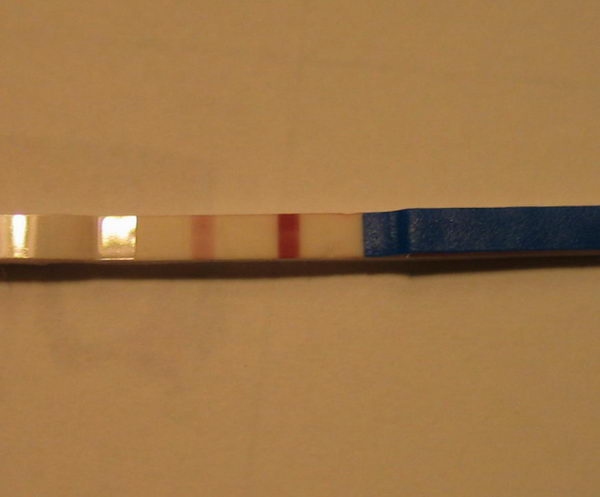

Húha!!! Ez nagyon bíztató! Drukkok!! Amúgy meg miért vársz erősebbet a 12. dpo-n?? 14. dpo előtt nem is érdemes igazán tesztelni. Úgyhogy ez tuti pozitív!!

Drukk!! De nem faldni, ha nem csíkos. 13. dpo még kicsit korai.